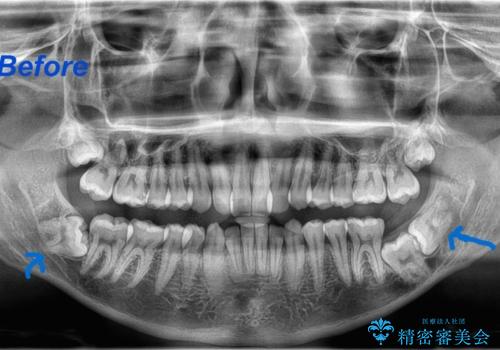

- 当院で矯正治療予定の患者さんです。下顎水平埋伏智歯による下顎第二大臼歯の歯周病やう蝕のリスクを考慮し抜歯をする事になりました。

今回の下顎水平埋伏智歯は歯茎と骨に埋まっていたので、麻酔をした後に歯茎を切開し骨を削って抜歯をしています。抜歯後、糸を縫って1週間後に抜糸に来ていただいています。抜歯後1週間は痛みとお顔の腫れがあり、度合いには個人差があります。